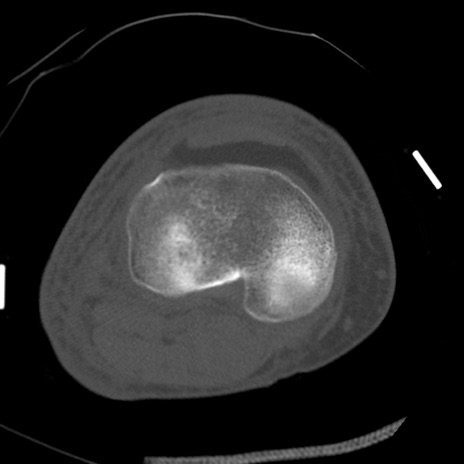

症例28 右膝関節CT(横断像)

右膝関節CT